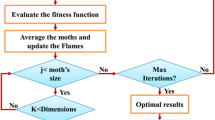

The new coronavirus has been declared as a global emergency. The first case was officially declared in Wuhan, China, during the end of 2019. Since then, the virus has spread to nearly every continent, and case numbers continue to rise. The scientists and engineers immediately responded to the virus and presented techniques, devices and treatment approaches to fight back and eliminate the virus. Machine learning is a popular scientific tool and is applied to several medical image recognition problems, involving tumour recognition, cancer detection, organ transplantation and COVID-19 diagnosis. It is proved that machine learning presents robust, fast and accurate results in various medical image recognition problems. Generally, machine learning-based frameworks consist of two stages: feature extraction and classification. In the feature extraction, overwhelmingly unsupervised learning techniques are applied to reduce the input data’s size. This step extracts appropriate features by reducing the computational time and increasing the performance of the classifiers. A classifier is the second step that aims to categorise the input. Within the proposed step, the unsupervised part relies on the feature extraction by using local binary patterns (LBP), followed by feature selection relying on factor analysis technique. The LBP is a kind of visual descriptor, mainly applied for image recognition problem. The aim of using LBP is to analyse the input COVID-19 image and extract salient features. Furthermore, factor analysis is a statistical technique applied to define variability among observed variables in less unnoticed variables named factors. The factor analysis applied to the LBP wavelet aims to select sensitive features from input data (LBP output) and reduce the size input. In the last stage, conic functions classifier is applied to classify two sets of data, categorising the extracted features by using LBP and factor analysis as positive or negative COVID-19 cases.

The proposed solution aims to diagnose COVID-19 by using LBP and factor analysis, based on conic functions classifier. The conic functions classifier presents remarkable results compared with these popular classifiers and state-of-the-art studies presented in the literature.